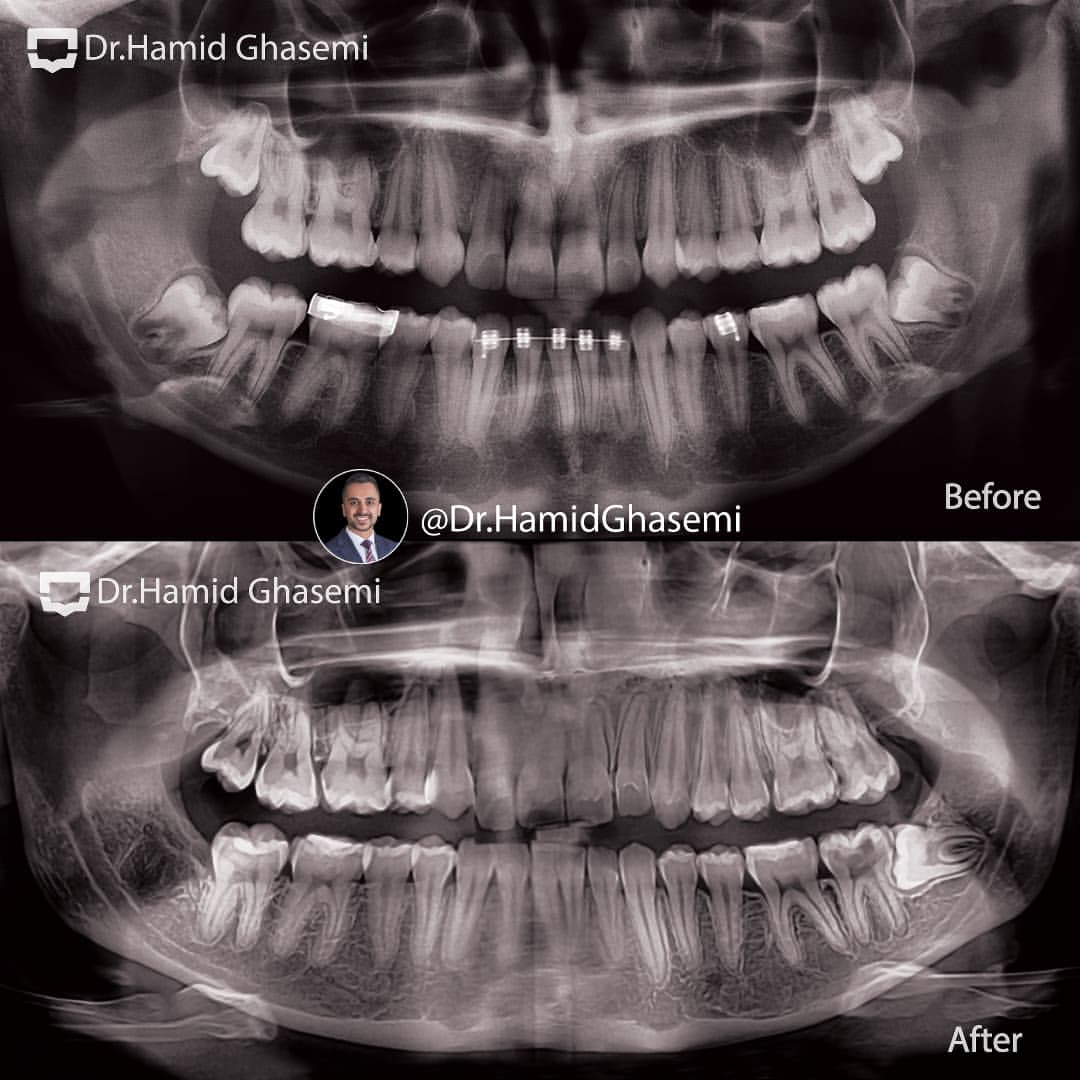

بیماری با سابقه درمان ارتودنسی ناموفق و کشیدن یکطرفه دندان پرمولر اول سمت راست که باعث ایجاد انحراف در آرچ فک بالا شده بود با شکایت انحراف فک بالا جهت درمان مجدد ارتودنسی مراجعه کردند.درمام مجدد ارتودنسی با کشیدن دندان عقل بالا در سمت چپ و دیستالیزیشن یکطرفه فک بالا با استفاده از اسکرو یکطرفه در ناحیه زایگوما در مدت ۲۱ ماه برای ایشان انجام شد.

Patient with history of unsuccessful orthodontic treatment with upper arch deviation due to Upper right premolar extraction came to my office with chief complain of upper arch deviation. Orthodontic re-treatment done for her by unilateral distalization of upper arch using unilateral infra-zygomatic screw after extraction of upper left 3rd molar in order to treat upper arch deviation within 21 months.